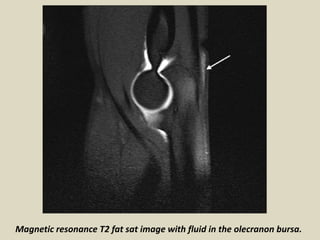

The olecranon bursa is a subcutaneous bursa that provides almost frictionless motion

between the skin, the subcutaneous tissues and the olecranon. Because of its superficial

location, it is a common site for injury, inflammation and infection. Repeated work-

related trauma results in bursitis as seen in “student's elbow” or “miner's elbow.

Olecranon bursitis is identified by clinical diagnosis, and imaging is rarely performed in

this context. In patients with advanced infection, MRI is sometimes requested to evaluate

abscesses or osteomyelitis. Incidental diagnosis of olecranon bursitis on ultrasound and

MRI is frequent from concomitant inflammation and effusion in the olecranon bursa

secondary to trauma, rheumatoid arthritis and other inflammatory diseases.

Magnetic resonance T2 fat sat image with fluid in the olecranon bursa.